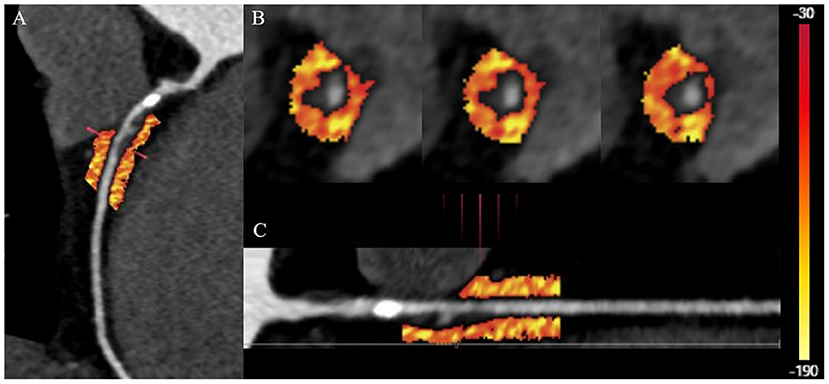

Vascular inflammation can promote the progression of coronary atherosclerosis and vulnerable plaque rupture, leading to the occurrence of ACS (64). Epicardial pericoronary adipose tissue (PCAT) is a special type of adipose tissue. It interacts with the adjacent vascular wall, regulates the cardiovascular biological function in a paracrine manner, and changes its phenotype in response to signals from vascular walls (82–86). Antonopoulos et al. (84) studied the gene expression, histology and CT imaging of adipose tissue samples collected during cardiac surgery, and considered that the CT density of adipose tissue (usually defined as −190 to −30 HU) reflects the balance of lipid and water phase, which is a marker of adipocyte size and lipid content. Inflammatory signals released by inflamed blood vessels are directly spread to PCAT, which can induce local lipolysis and inhibit fat formation, and also increase microvascular permeability, thus promoting perivascular edema. With the decrease of lipid content and morphology in adipocytes of PCAT, the lipid phase in adipose tissue decreases and the water phase increases, resulting in different gradients of adipocytes around the coronary artery. A further study confirmed that PCAT CT attenuation measured by CCTA can detect vascular inflammation confirmed by biopsy, and the fat attenuation index (FAI) was proposed (84). Pericoronary FAI was used to track and quantify the composition changes of PCAT by evaluating the spatial changes of peripheral fat attenuation by CCTA, which was the average density of adipose tissue in the target area (84) (Figure 4), reflecting inflammatory burden of target coronary segment (A higher pericoronary FAI was associated with a higher inflammatory burden).

Figure 4. Quantification of PCAT CT attenuation of low-attenuation plaques in the proximal-mid right coronary artery. (A) The multiplanar reconstructed image of PCAT measured with the range from −190 to −30 HU. (B) Cross-section images of PCAT measure. (C) Straightened image of PCAT measure. PCAT, pericoronary adipose tissue; HU, Hounsfield units.

Inflammation of adipose tissue around the plaque will directly affect the formation and stability of coronary plaque. Therefore, PCAT attenuation measured by CCTA is a promising indicator for identifying high-risk plaques. In patients with ACS, cases of PCAT stranding have been reported around culprit lesions (87). Goeller et al. retrospectively recruited 19 patients with ACS and 16 patients with stable CAD (88). They found that culprit lesions were associated with increased FAI around the lesions. The frequency of pericoronary FAI ≥-68.2 HU of culprit lesions in ACS is higher, which can be used as a potential cut-off value to distinguish culprit lesions and non-culprit lesions. Therefore, combining the characteristics of high-risk plaques with the FAI around the plaques can be more reliable in identifying the high-risk plaques leading to ACS. Goeller et al. further studied the correlation between pericoronary FAI and coronary plaque progression (89). They found that the increased non-calcified plaque burden was related to the increased FAI, on the contrary, the decreased non-calcified plaque burden was related to the decreased FAI, and FAI ≥ −75 HU around the proximal end of right coronary artery (RCA) was an independent predictor of increased load of non-calcified plaques and total plaques. Therefore, PCAT is helpful to identify patients with high risk of plaque progression.